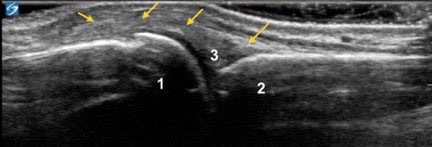

Hand 2nd MCP Joint Long Axis Image

1. Distal Metacarpal Head

2. Proximal Phalanx

3. Joint Homologue

Arrows: Joint Capsule